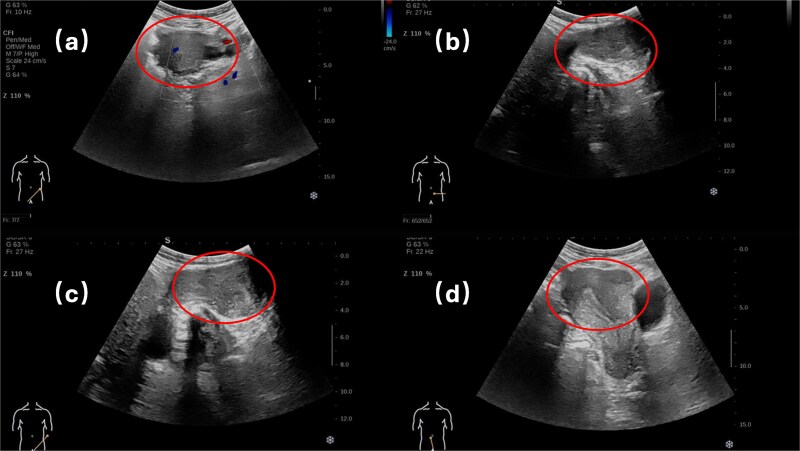

起源于子宫圆韧带的腺肌瘤是一种非常罕见的病理实体。考虑到圆形韧带穿过腹股沟管的解剖过程,这种结构的病理病变在临床上可能表现为盆腔或腹股沟肿块,因此需要从广泛的其他病理情况中进行区分。具有特殊临床意义的是,引起腹股沟疝的腺肌瘤相关表现非常罕见,最终的诊断确认取决于组织病理学证实。我们在此报告一例腹股沟管内原发性圆形韧带腺肌瘤,旨在提高临床认识,为同类临床情况的诊断和治疗决策提供循证指导和优化。

Adenomyoma originating from the round ligament of the uterus represents a remarkably uncommon pathological entity. Considering the anatomical course of the round ligament through the inguinal canal, pathological lesions in this structure may clinically present as pelvic or inguinal masses, thereby requiring differentiation from a broad spectrum of alternative pathological conditions. Of particular clinical significance, adenomyoma-associated manifestations causing inguinal hernia remain exceedingly rare, with definitive diagnostic confirmation contingent upon histopathological verification. We herein present a case of primary round ligament adenomyoma localized within the inguinal canal, with the objective of enhancing clinical awareness and providing evidence-based guidance and optimizing diagnostic and therapeutic decision-making in comparable clinical scenarios.